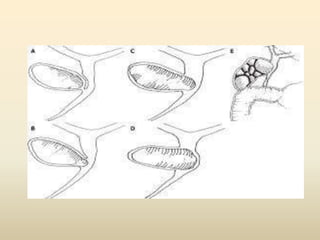

Classification

• Type I : external compression of the bile duct by a large stone or stones

impacted in the cystic duct or in the Hartmann’s pouch

• Type II : cholecystobiliary fistula resulting from erosion of the bile duct

wall by a gallstone, the fistula must involve less than one-third of the

circumference of the bile duct

• Type III : cholecystobiliary fistula involving up to two-thirds of the bile duct

circumference

• Type IV : cholecystobiliary fistula with complete destruction of the bile

duct wall with the gallbladder completely fused to the bile duct forming a

single structure with no recognizable dissection planes between both

biliary tree structures

• Mirizzi type V, includes the presence of a cholecystoenteric fistula

together with any other type of Mirizzi

• Type Va : includes a cholecystoenteric fistula without gallstone ileus

• Type Vb : cholecystoenteric fistula complicated by gallstone ileus

Classification • Type I :external compression of the bile duct by a large stone or stones impacted in the cystic duct or in the Hartmann’s pouch • Type II : cholecystobiliary fistula resulting from erosion of the bile duct wall by a gallstone, the fistula must involve less than one-third of the circumference of the bile duct • Type III : cholecystobiliary fistula involving up to two-thirds of the bile duct circumference • Type IV : cholecystobiliary fistula with complete destruction of the bile duct wall with the gallbladder completely fused to the bile duct forming a single structure with no recognizable dissection planes between both biliary tree structures • Mirizzi type V, includes the presence of a cholecystoenteric fistula together with any other type of Mirizzi • Type Va : includes a cholecystoenteric fistula without gallstone ileus • Type Vb : cholecystoenteric fistula complicated by gallstone ileus